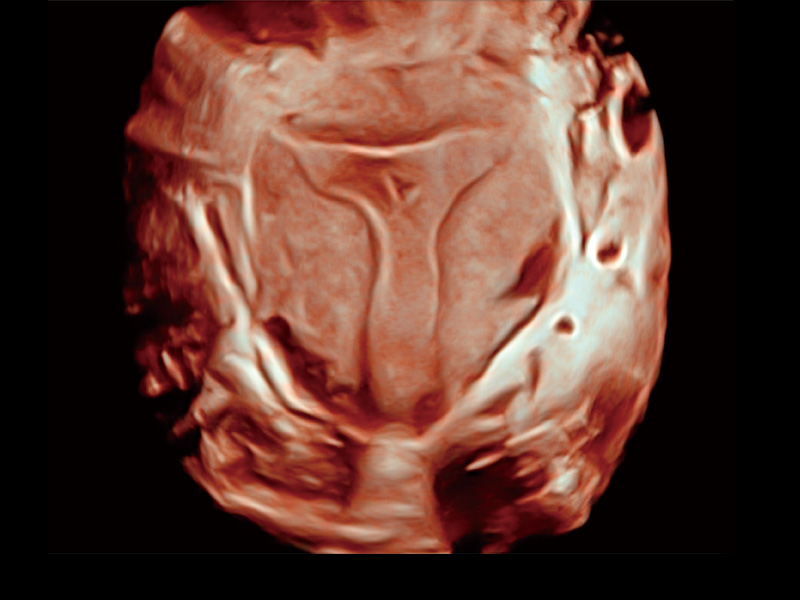

腔内容积探头

腔内三维成像技术获得显著提升,超大扇角在满足日常基础扫查的同时,支持卵泡自动测量及多种三维渲染模式,为您提供更多的诊断信息,尤其是在子宫畸形的诊断,内膜及肿瘤占位观测中起到了重要的作用。

临床图

单角子宫